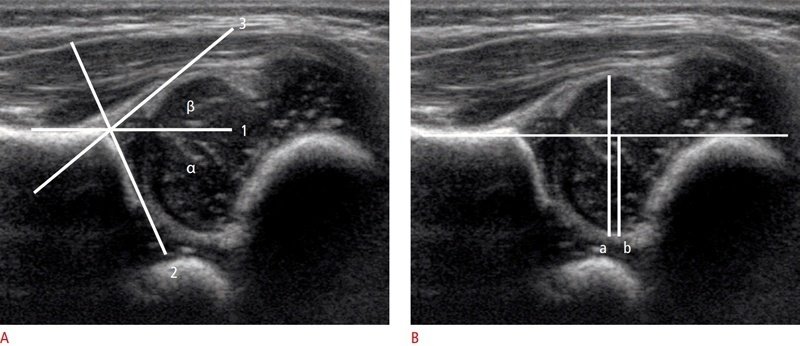

Pediatrik kalça ultrasonu kalçanın gelişimsel eksikliklerini değerlendirmek amacıyla genellikle 1-3 aylık bebeklere belli pozisyonlarda yapılan incelemedir. Bu incelemede amaç uyluk kemiğinin başının, leğen kemiği ile ilişkisini değerlendirebilmektir. Bu değerlendirme hem gözle hem de parametrik olarak yapılır.

İncelemede parametrik ölçülerden alfa ve beta açısı önemlidir. Alfa açısının 60 derece üzerinde olması kalça gelişiminin genel olarak normal seyrettiğini düşündürür. 60 derecenin altı ise dereceye göre bir sınıflama yapılır ve buna göre takip ve tedavi planlanır.

Sınıflamada ilk evrelerde olan kalçalarda 1 aylık aralıkla takip ve ara bezi gibi tedaviler gerekirken, ileri evrelerde kalçalarda bandajlar ve cerrahiye uzanan aralıkta tedavi spektrumu mevcuttur.

Şekilde normal kalça eklem gelişimi olan alfa açısı 60 derecenin üzerinde, beta açısı 55 derecenin altında olan bir bebeğin kalça ultrasonu görüntüsü yer alıyor.